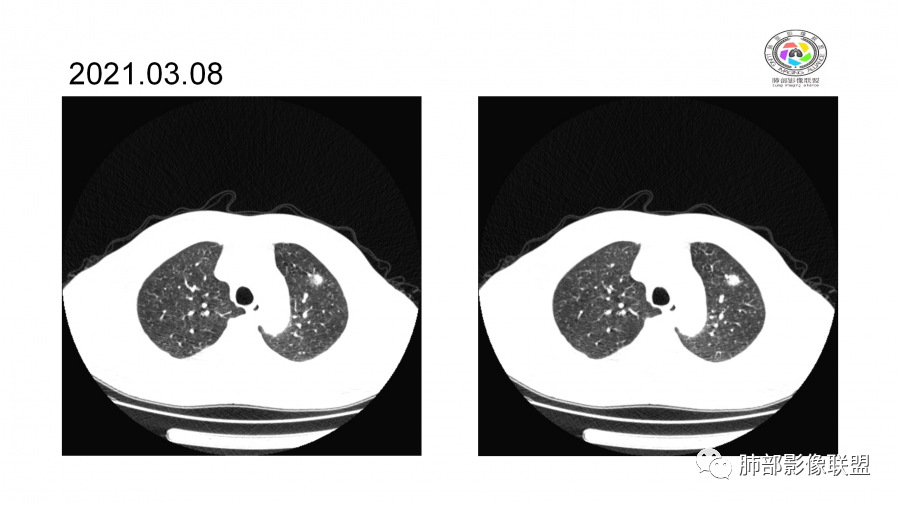

10天后:病灶继续吸收好转

伴随少量胸水

应该与气道无关

符合间质、血管来源病变

此起彼伏

有肾功能不全

支持与肾病相关

警惕血管炎

中年男性,高血压,肾功能衰竭,贫血病史,尿潜血阳性。3.8双肺野多发斑片磨玻璃实变影,结节影,边缘模糊,周围有晕征,内见支气管充气征,主要沿支气管血管束分布,部分胸膜下分布,3.12号病灶有吸收好转,4.8号斑片实变影基本吸收,主要沿支气管血管束分布结节影,边缘平直收缩,4.28病灶大部分吸收好转,双肺支气管血管束增粗,有少量结节影。考虑ANCA相关性血管炎可能性大,第一次片子觉得隐球菌不排除,但是后面没有抗真菌治疗就吸收了,觉得隐球菌可能性不大。

胸部CT:双肺多发实性斑片影,散在GGO。实性斑片周围可见晕征、边缘模糊不清,病灶于肺外围区域优势分布。肺门区血管影增粗,支气管套袖,目测肺动脉增粗。3月、4月复查肺内实性斑片病灶呈游走性,此起彼伏。